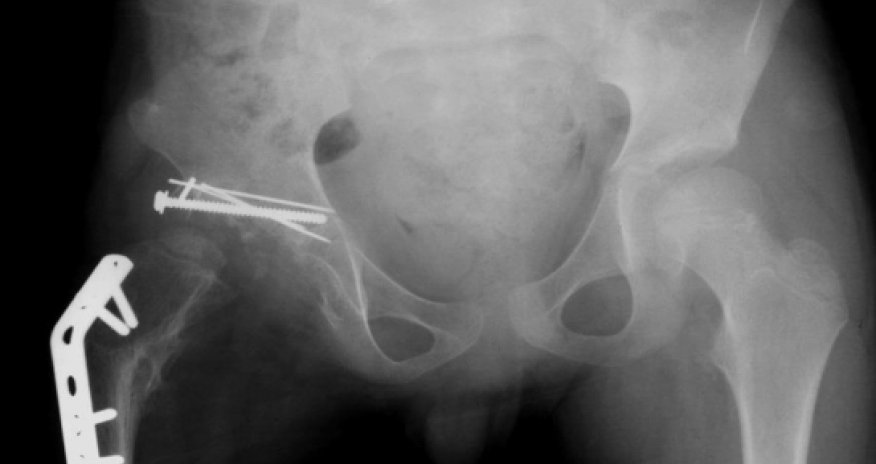

Norwegian artist Alexander Selvik Wengshoel claims to have eaten his own hip “on a whim” and presented the bone in his graduate exhibition.Yes, conceptual art has reached a whole new level, with the 25-year-old describing the bizarre turn of events at the opening of his Tromso Academy of Contemporary Art show. Wengshoel took the body part home after a hip replacement operation, boiled it to loosen the meat and ate it with potato gratin and a glass of wine.His girlfriend (who may or may not still be his girlfriend) was at work while he dined on the “goaty” meat.“When I got home I sat in my living room and suddenly I had a whim that I should cook the meat,” he told The Local. “I resolved to have this really nice moment, with me and my hip bone."It’s not every day I will have a piece of human flesh which is mine and which it is possible to eat. So I had a little taste and then I thought, ‘That’s really nice’.“It had this flavour of wild sheep, if you take a sheep that goes in the mountains and eats mushrooms.”Wengshoel, who was born with a deformed hip and suffered many failed operations during childhood, had spent most of his life in a wheelchair or on crutches before undergoing the life-changing surgery aged 21.Now, his meatless hip bone and video footage of his operation are displayed for viewers to gain insight into his cathartic story.“It had been such a problem for me for over 20 years and it was just a way of making it better again,” he said. “It had been so hard to have it in my body, and when I took it out, it turned into something else, something romantic. It was a natural process I felt I had to do to move on.”Not everyone has seen Wengshoel’s project as ‘art’, with some people reacting in a “really p***ed off” manner. But the artist insists that sparking people into thinking about their own bodies and their personal view of their bodies is important.“I just work with my own body, that is my canvas,” he said. “Previously I wasn’t given any choice by doctors but now I can take control myself and decide what I want to do with it.”(independent.co.uk)Bakudaily.az